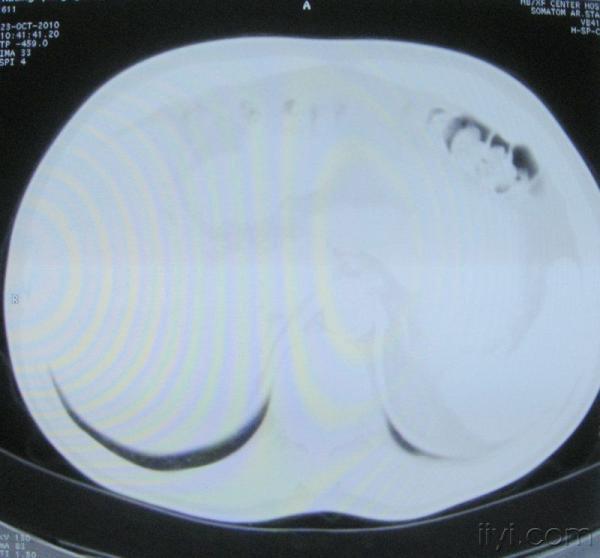

男。60岁,胸片示支气管炎治疗后复查CT。

你指那个肯定是淋巴结,中央系坏死,这很常见,特别在双侧腹股沟会经常看到。这个双侧腋窝及纵隔见多发小淋巴结征。

根据位置考虑应该是淋巴结,密度不均,是因为肿大的淋巴结中心液化坏死